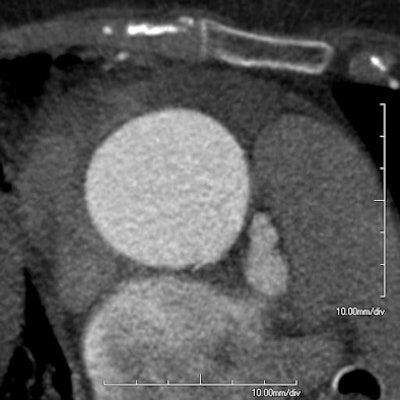

| At ECG-gated cornary CTA, a small defect can be seen in the aortic wall of a 74-year-old woman referred for suspected pulmonary embolism. The lesion was found to correspond to a 12-mm supercoronary tear in the aortic wall at surgery. Image courtesy of Dr. Sebastian Schotten. |